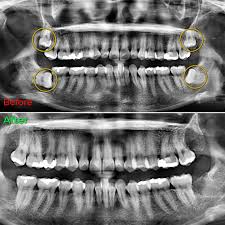

Wisdom teeth, also known as third molars, often become impacted or grow at angles that can cause pain, infection, or damage to adjacent teeth. Removal is typically recommended when there isn't enough space in the jaw for them to erupt properly or when they are causing clinical complications.

Wisdom teeth X-ray Wisdom tooth extraction procedure